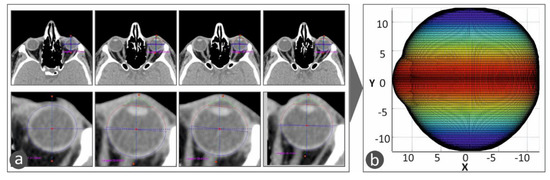

This 3D geometric model of the patient’s eye was employed for the development of a macular buckle implant that fits accurately to the specific eye’s geometry. Based on the results presented in the literature [17], a T-shaped macular buckle was selected. A software tool was developed in which the user selects the desirable starting and ending points of the implant in the outer surface of the eye’s geometry. This defines a path on the outer surface of the eye that the macular buckle will follow. Then, the point of interest of the macular buckle is selected on this path, and, finally, the required pressure that the macular buckle should apply to the eye is also selected (Figure 4). Figure 4a–d show the procedure for the determination of the trajectory the macular buckle geometry should follow. Points are defined by the user in the macula position in the eye and the buckle geometry is defined according to the path defined by these points in space selected in the outer surface of the eye. The macula position was determined according to the literature (2.5 times the optic disk diameter) [18].

Figure 4.

The procedure for the definition of the macular buckle implant trajectory and shape in the software developed in the current work: (a–d) show the procedure for the determination of the trajectory the macular buckle geometry should follow. Points are defined by the user in the macula position in the eye and the buckle geometry is defined according to the path defined by these points in space selected in the outer surface of the eye.